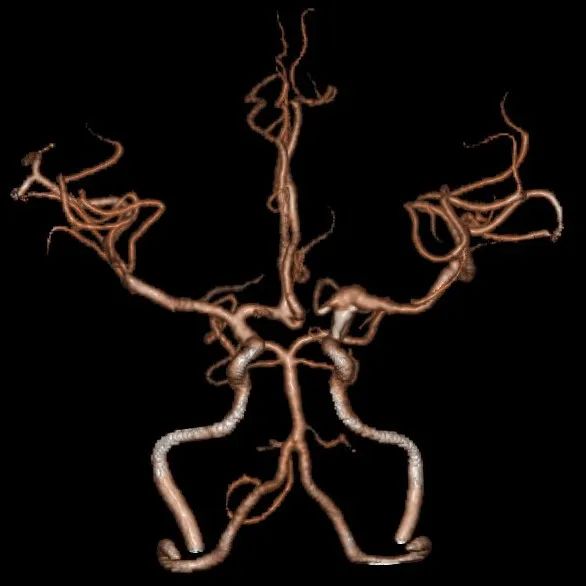

术前影像入院前头颅CTA提示:左侧颈内动脉C7段末端动脉瘤。

入院后查高分辨核磁显示:左侧颈内动脉交通段、左侧大脑前动脉A1段及左侧大脑中动脉M1段管壁明显强化,左侧颈内动脉交通段及左侧大脑中动脉M1段管腔内可见强化内膜片影,考虑左侧颈内动脉交通段夹层动脉瘤累及M1、A1段(左侧颈内动脉交通段及左侧大脑中动脉M1段管腔扩张,左侧大脑前动脉A1管腔明显狭窄)。